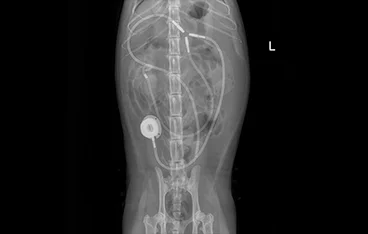

비뇨기폐색(요관폐색 & 요도폐색)

SUB, ureteral stent, 요도루조성술(PU)

• SUB

• 요관스텐트(ureteral stent)

• 요도루조성술(PU)